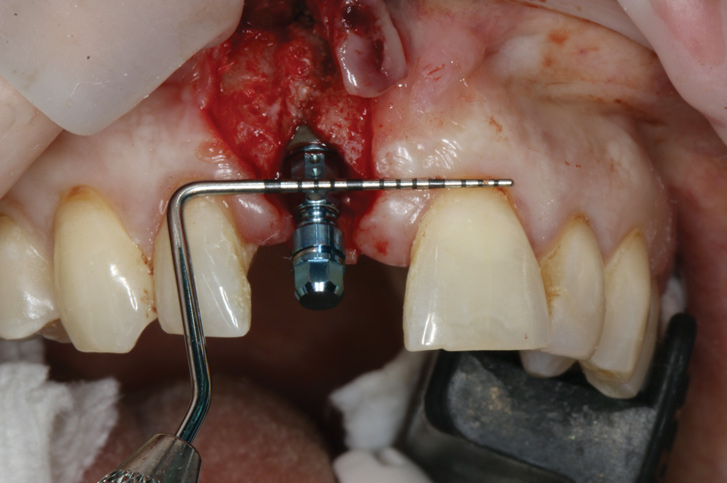

(17.) Implant placed 1-mm distal to the midline of the edentulous space, corresponding with the planned location of the gingival zenith. Note the lack of sufficient bone buccal to the implant that necessitated further grafting.

Figure 17

Prior to the initiation of the surgery, the surgical guide was tried in to confirm proper seating and stability (Figure 15). A flapless approach was not considered because the need for further bone grafting at the time of implant placement had been anticipated through the digital planning. A slightly palatal crestal incision was made, followed by two vertical incisions on the mesial and distal aspects of the edentulous site in order to preserve the papilla and avoid additional esthetic compromise to the anterior sextant. Next, a full-thickness flap was elevated to facilitate removal of the tenting screw and permit visualization of the buccal plate (Figure 16). A standard guided protocol was followed to place the implant, and its final position mirrored that of the digital plan. As predicted, the prosthetically driven implant position resulted in an insufficient buccal plate (Figure 17); therefore, additional guided bone regeneration was performed to reinforce the area and prevent future breakdown (Figure 18 and Figure 19). Making periosteal incisions could have compromised the blood supply to the flap, so instead, it was stretched in order to achieve tension free coronal advancement.31The flap was secured utilizing horizontal mattress sutures with additional supportive interrupted sutures to ensure primary closure (Figure 20). An immediate postoperative periapical radiograph (Figure 21) and CBCT scan (Figure 22) were taken, demonstrating a final implant position centered with the planned location of the gingival zenith.